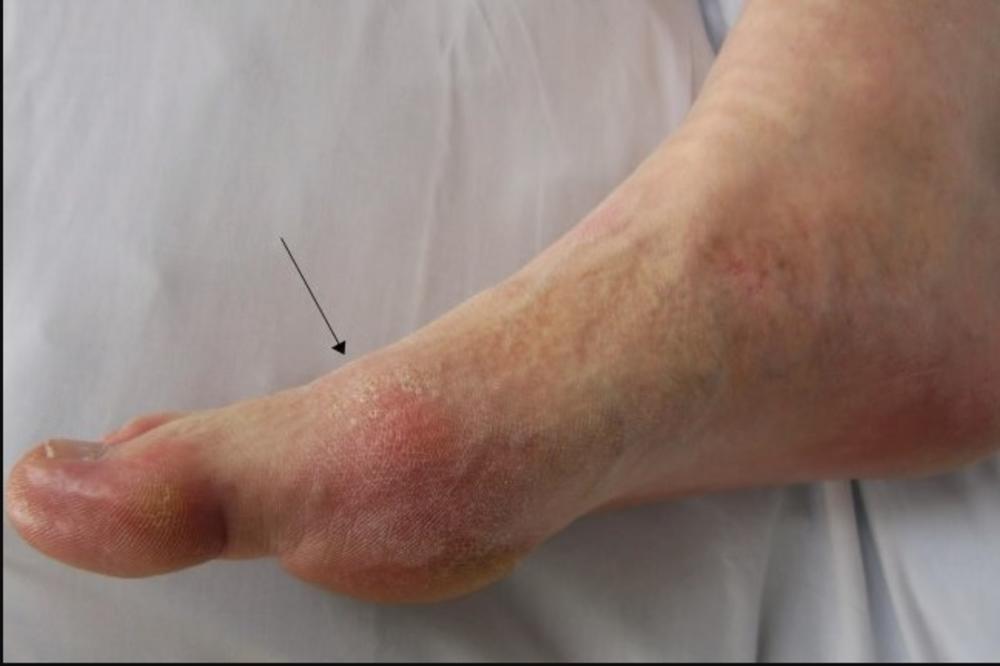

Roditelji su odveli dete u bolnicu deset dana nakon što su joj se na tabanima pojavili čvorići i povrede, a lekari su joj dijagnostikovali infekciju koju izaziva Tunga penetrans, parazit koji se gnezdi u koži.

Ženka buve se "ukopava" u kožu, najčešće na prstima stopala, tabanima, ili petama. Dok usisava krv, njeno telo brzo raste, izazivajući svrab, zapaljenje i bol.

Infekcija povrede se pojačava ukoliko je ćelija zaražena drugim sojem bakterije, pa se na stopalima stvaraju apscesi i gnoj.